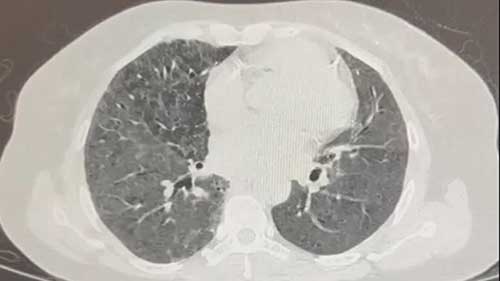

经支气管冷冻肺活检

根据临床体征,在硬质支气管镜下进行冷冻肺活检需要三个步骤。

经支气管镜活检

在进行经支气管镜活检时,我们首先需要选择活检位置,然后置入支气管镜进行操作,最后取出样本进行活检。